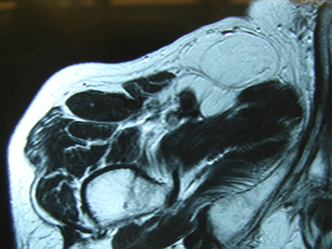

脂肪腫(良性)